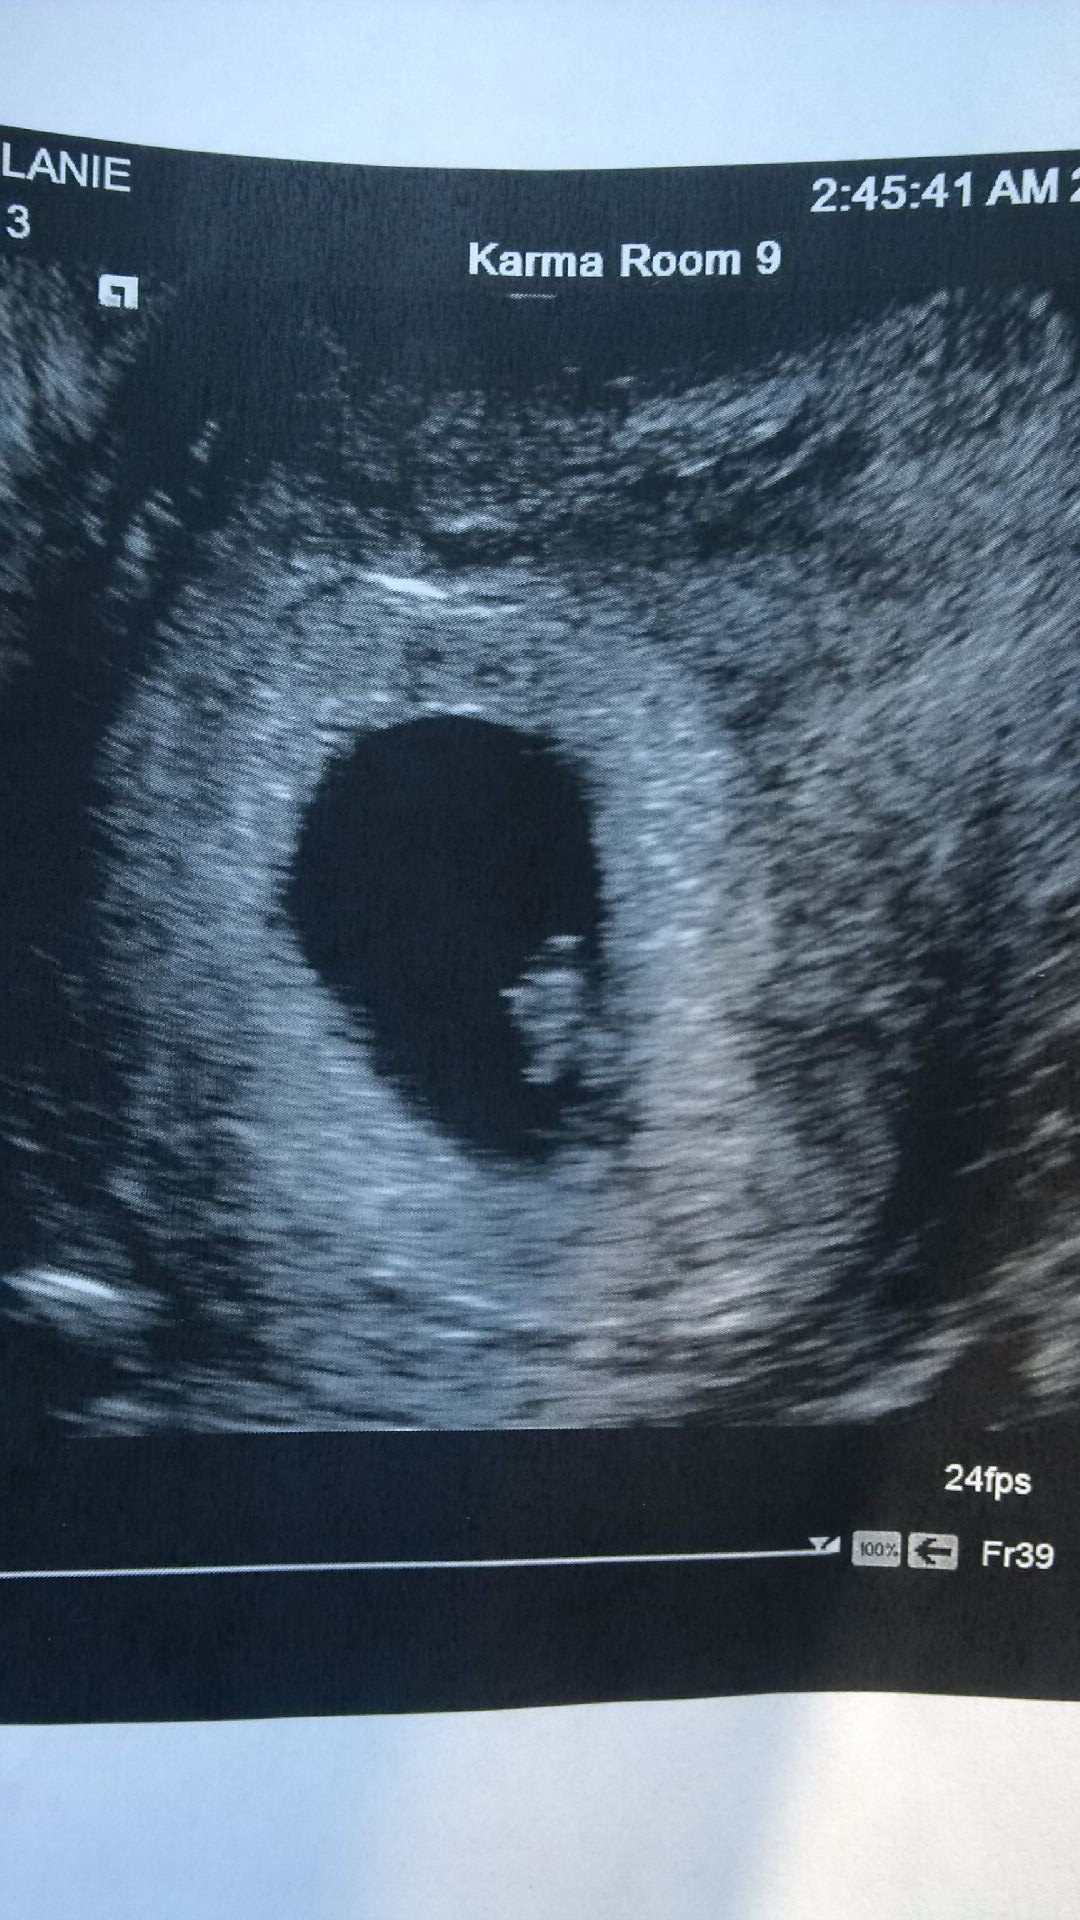

I actually emailed Ramzi himself and he said, at first, 95% true transverse and left indicating girl. However, last week he said he looked more closely and now doesn't know if the image is transvag or sagittal. Can anyone point out my bladder?

Huge thanks in advance! I'm going crazy with wonder!

Attachment 21599